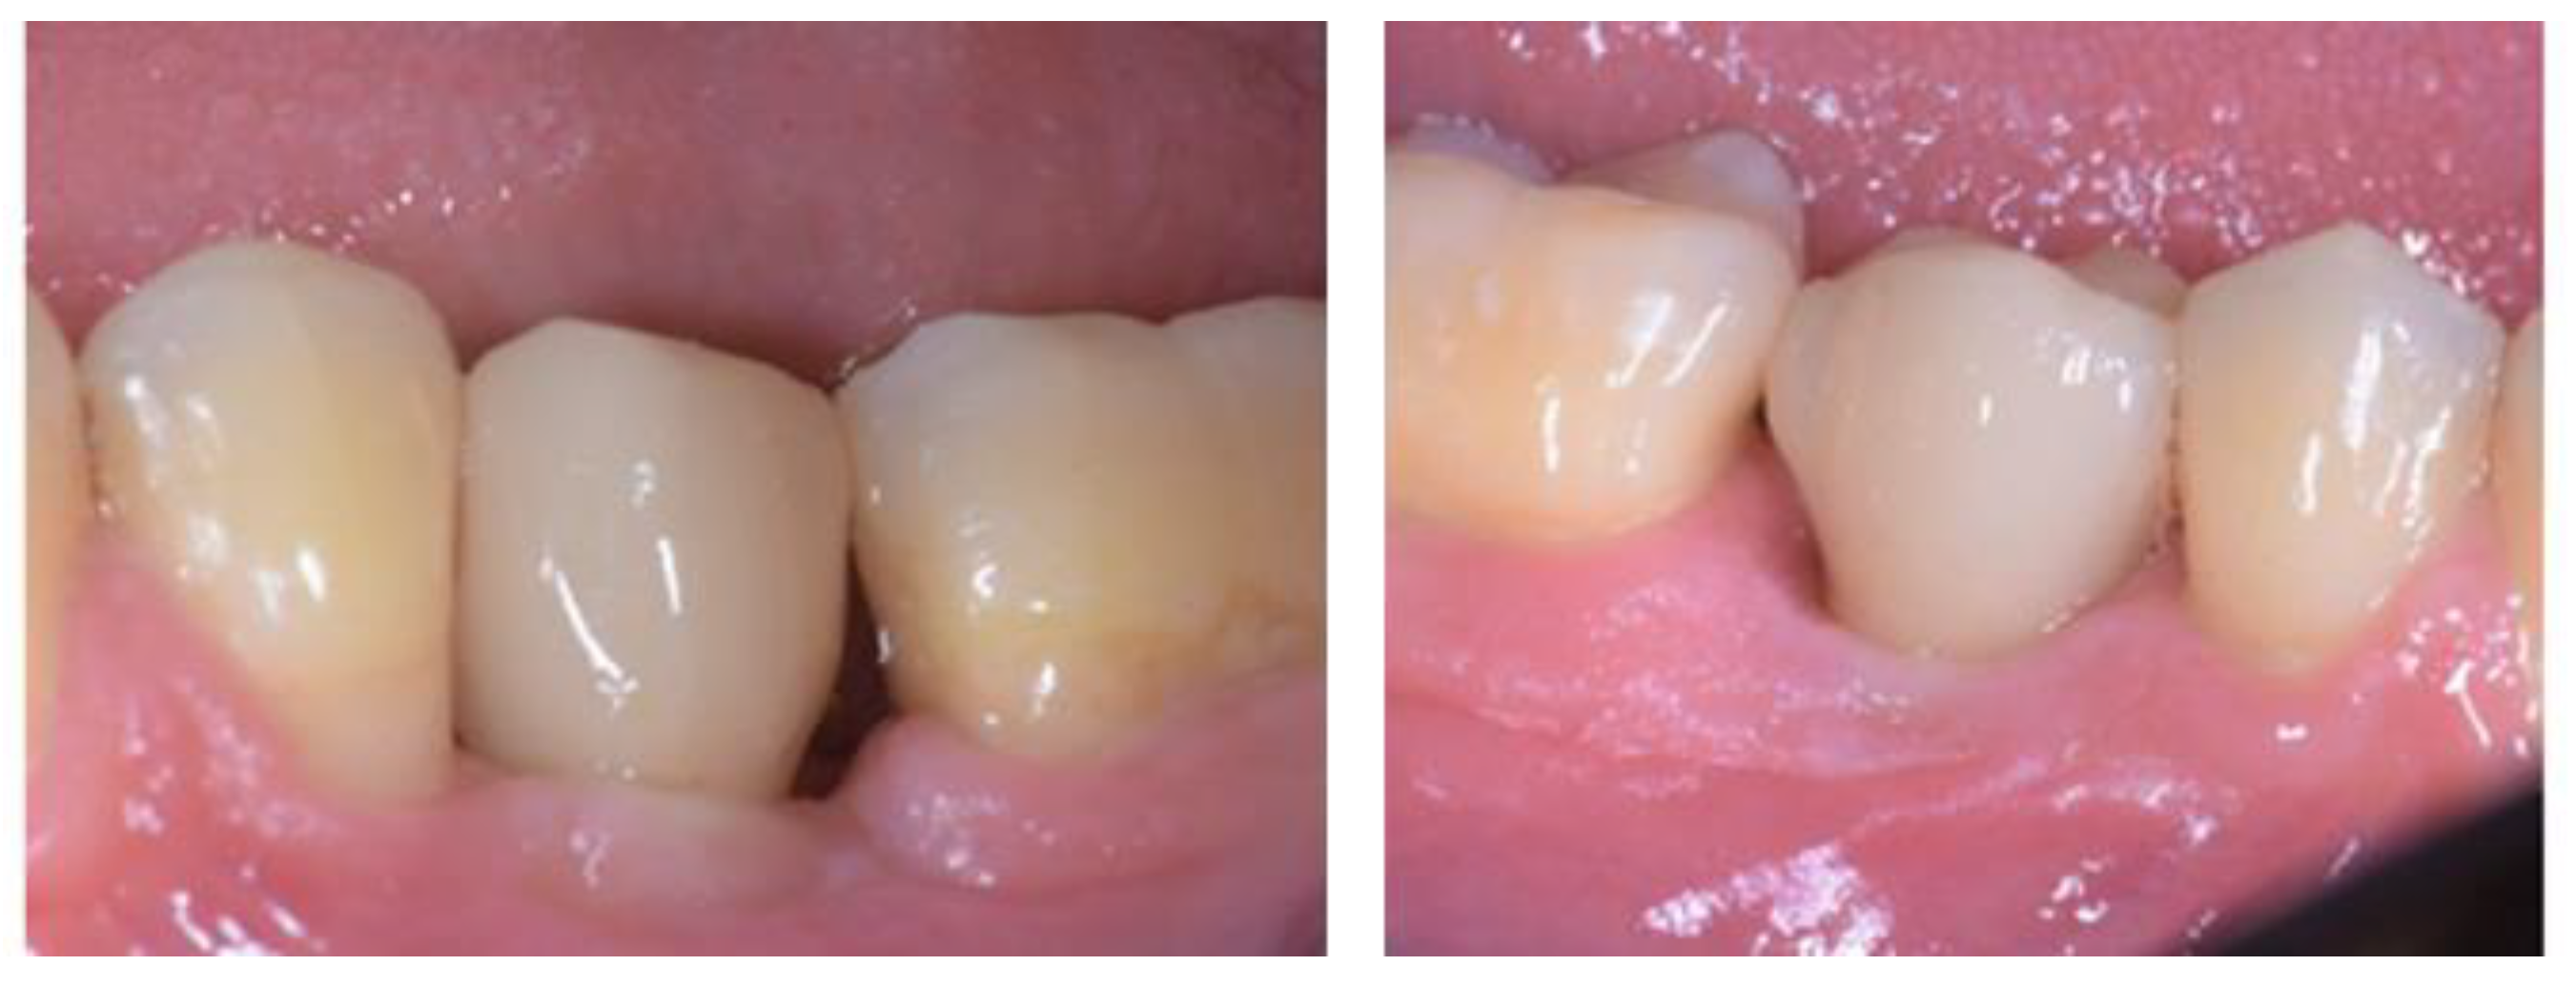

2.5. Individual Cases Description

- Case 2:

- Case 3:

- Case 4:

- Case 5: